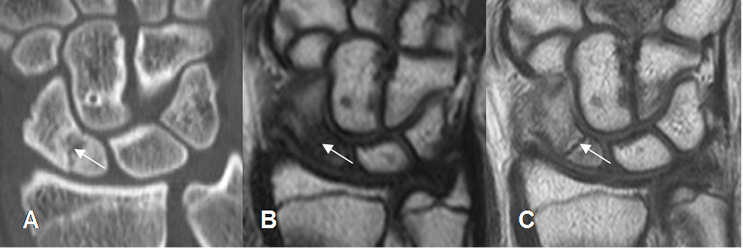

Fig 24 A. Osteonecrosis.

A: Rx AP. Zonas densas de etiología inespecífica, en ambos cóndilos femorales.

B: RM sagital en T1, C: RM sagital en T2 y D: RM sagital en STIR. Lesión geográfica en la parte posterior del cóndilo femoral lateral, hipointensa en T1 y T2 e hiperintensa en STIR, por osteonecrosis de evolución subaguda. Adicionalmente hay lesiones osteocondrales en la patela y la parte anterior del cóndilo.

Fig 25. Osteonecrosis de escafoides.

A: TAC reconstrucción coronal. Fractura transversa en el tercio inferior del escafoides.

B: RM coronal en T1. El polo inferior del escafoides es mas hipointenso, lo que hace sospecha osteonecrosis.

C: RM coronal en T1 con contraste. El hueso escafoides presenta realce homogéneo, indicando viabilidad.